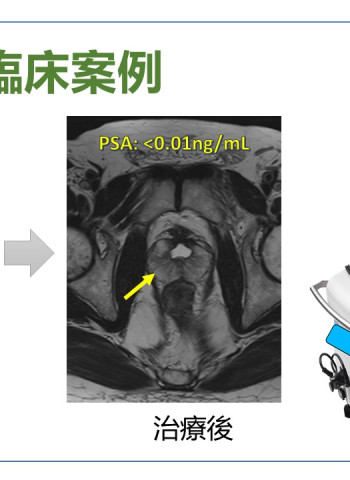

奇美醫院海福刀無創手術 結合即時影像 精準摧毀癌細胞